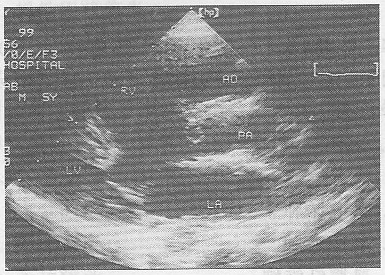

1.女,25岁,停经55天,腹痛、阴道出血1周。尿妊娠试验阴性。结合超声图像(彩图34),最可能的诊断为

正确答案:D 解题思路:宫腔内可见无回声暗区,其内未见胚芽及胎心搏动。患者有停经,腹痛,阴道流血等流产症状,尿HCG阴性。